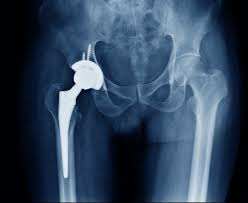

Musculoskeletal issues such as arthritis, avascular necrosis, knee pain, and hip degeneration often require advanced surgical solutions. Under Ayushman Bharat facilities in Seoni, Varunam Super Speciality Hospital provides cashless orthopedic care. This includes hip replacement, knee replacement, trauma surgery, and fracture fixation.

Dr. Utsav Agrawal leads the orthopedic team, ensuring every surgical plan is precise and tailored. Moreover, modern surgical tools help achieve better alignment, reduced pain, and faster recovery. Because the PMJAY scheme covers implants and surgery costs, eligible patients can undergo joint replacement without financial strain.

Q3. Is hip or knee replacement included under Ayushman Bharat?

Yes, eligible hip and knee replacements are part of the cashless facility.